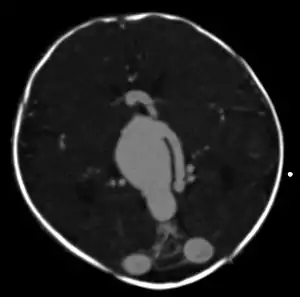

Axial image from computerized tomography angiogram showing arteriovenous communication in vein of Galen malformation

An AVM diagnosis is established by neuroimaging studies after a complete neurological and physical examination.[4][9] Three main techniques are used to visualize the brain and search for AVM: computed tomography (CT), magnetic resonance imaging (MRI), and cerebral angiography.[9] A CT scan of the head is usually performed first when the subject is symptomatic. It can suggest the approximate site of the bleed.[2] MRI is more sensitive than CT in the diagnosis of AVMs and provides better information about the exact location of the malformation.[9] More detailed pictures of the tangle of blood vessels that compose an AVM can be obtained by using radioactive agents injected into the blood stream. If a CT is used in conjunctiangiogram, this is called a computerized tomography angiogram; while, if MRI is used it is called magnetic resonance angiogram.[2][9] The best images of an AVM are obtained through cerebral angiography. This procedure involves using a catheter, threaded through an artery up to the head, to deliver a contrast agent into the AVM. As the contrast agent flows through the AVM structure, a sequence of X-ray images are obtained.[9]